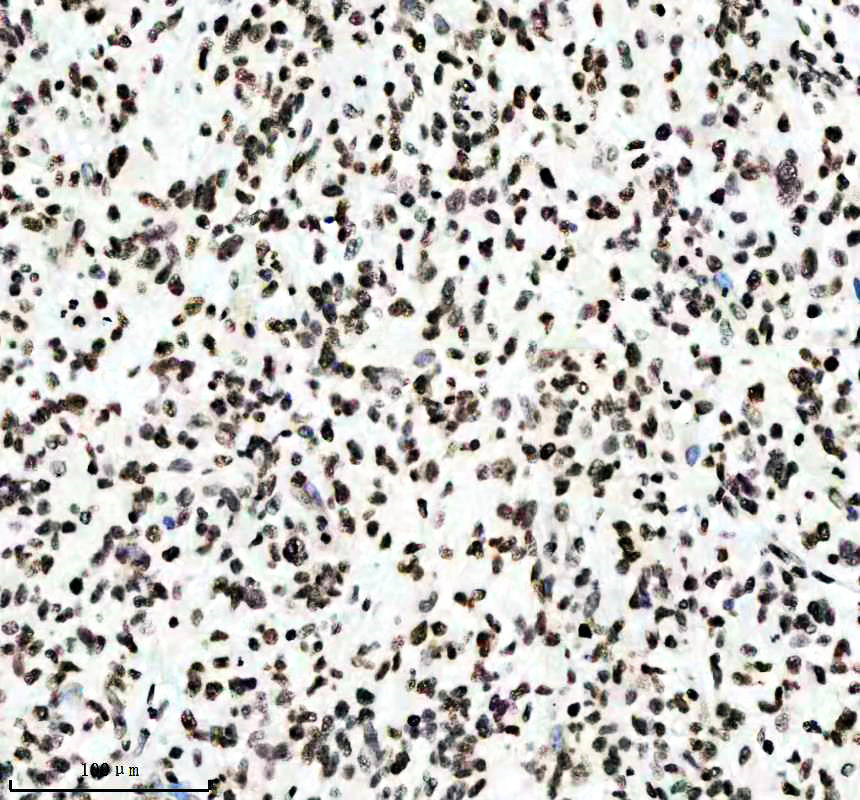

IHC analysis of Histone H3 (acetyl K14) using anti-Histone H3 (acetyl K14) antibody (BM4151) .

Histone H3 (acetyl K14) was detected in a paraffin-embedded section of human rectal cancer tissue. The tissue section was incubated with rabbit anti-Histone H3 (acetyl K14) Antibody (BM4151) at a dilution of 1:200 and developed using HRP Conjugated Rabbit IgG Super Vision Assay Kit (Catalog # SV0002) with DAB (Catalog # AR1027) as the chromogen.